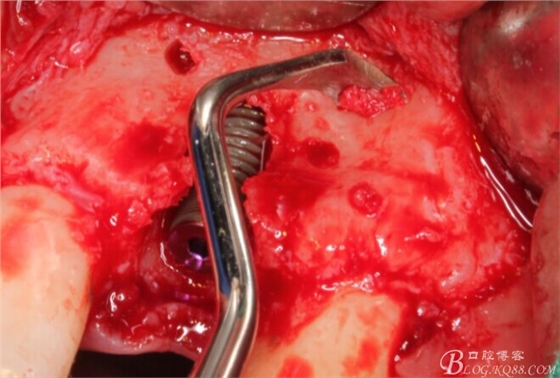

旋入一長(zhǎng)兩短3顆鈦釘。

將自體骨與BIO-OOS骨粉混合植到術(shù)區(qū),蓋生物膜。